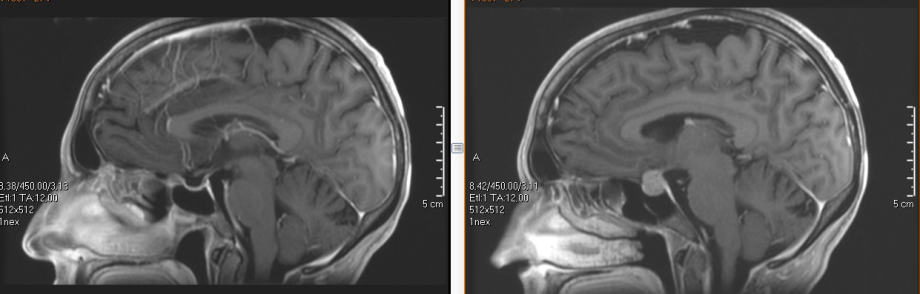

Pituitary surgery

Pituitary lesions have been classically addressed through sublabial incisions and an operating microscope. In recent years, endoscopic techniques have been developed that provide two main advantages: they allow the natural nostrils to be used, avoiding any incision and preserving the nasal mucosa better, and they offer a much closer and sharper view of the area by being able to introduce the optic into the breast of the tumor. These two advantages translate into the patient in more postoperative

Our team is a pioneer in the introduction of endoscopic techniques for the treatment of sellar lesions with excellent results.